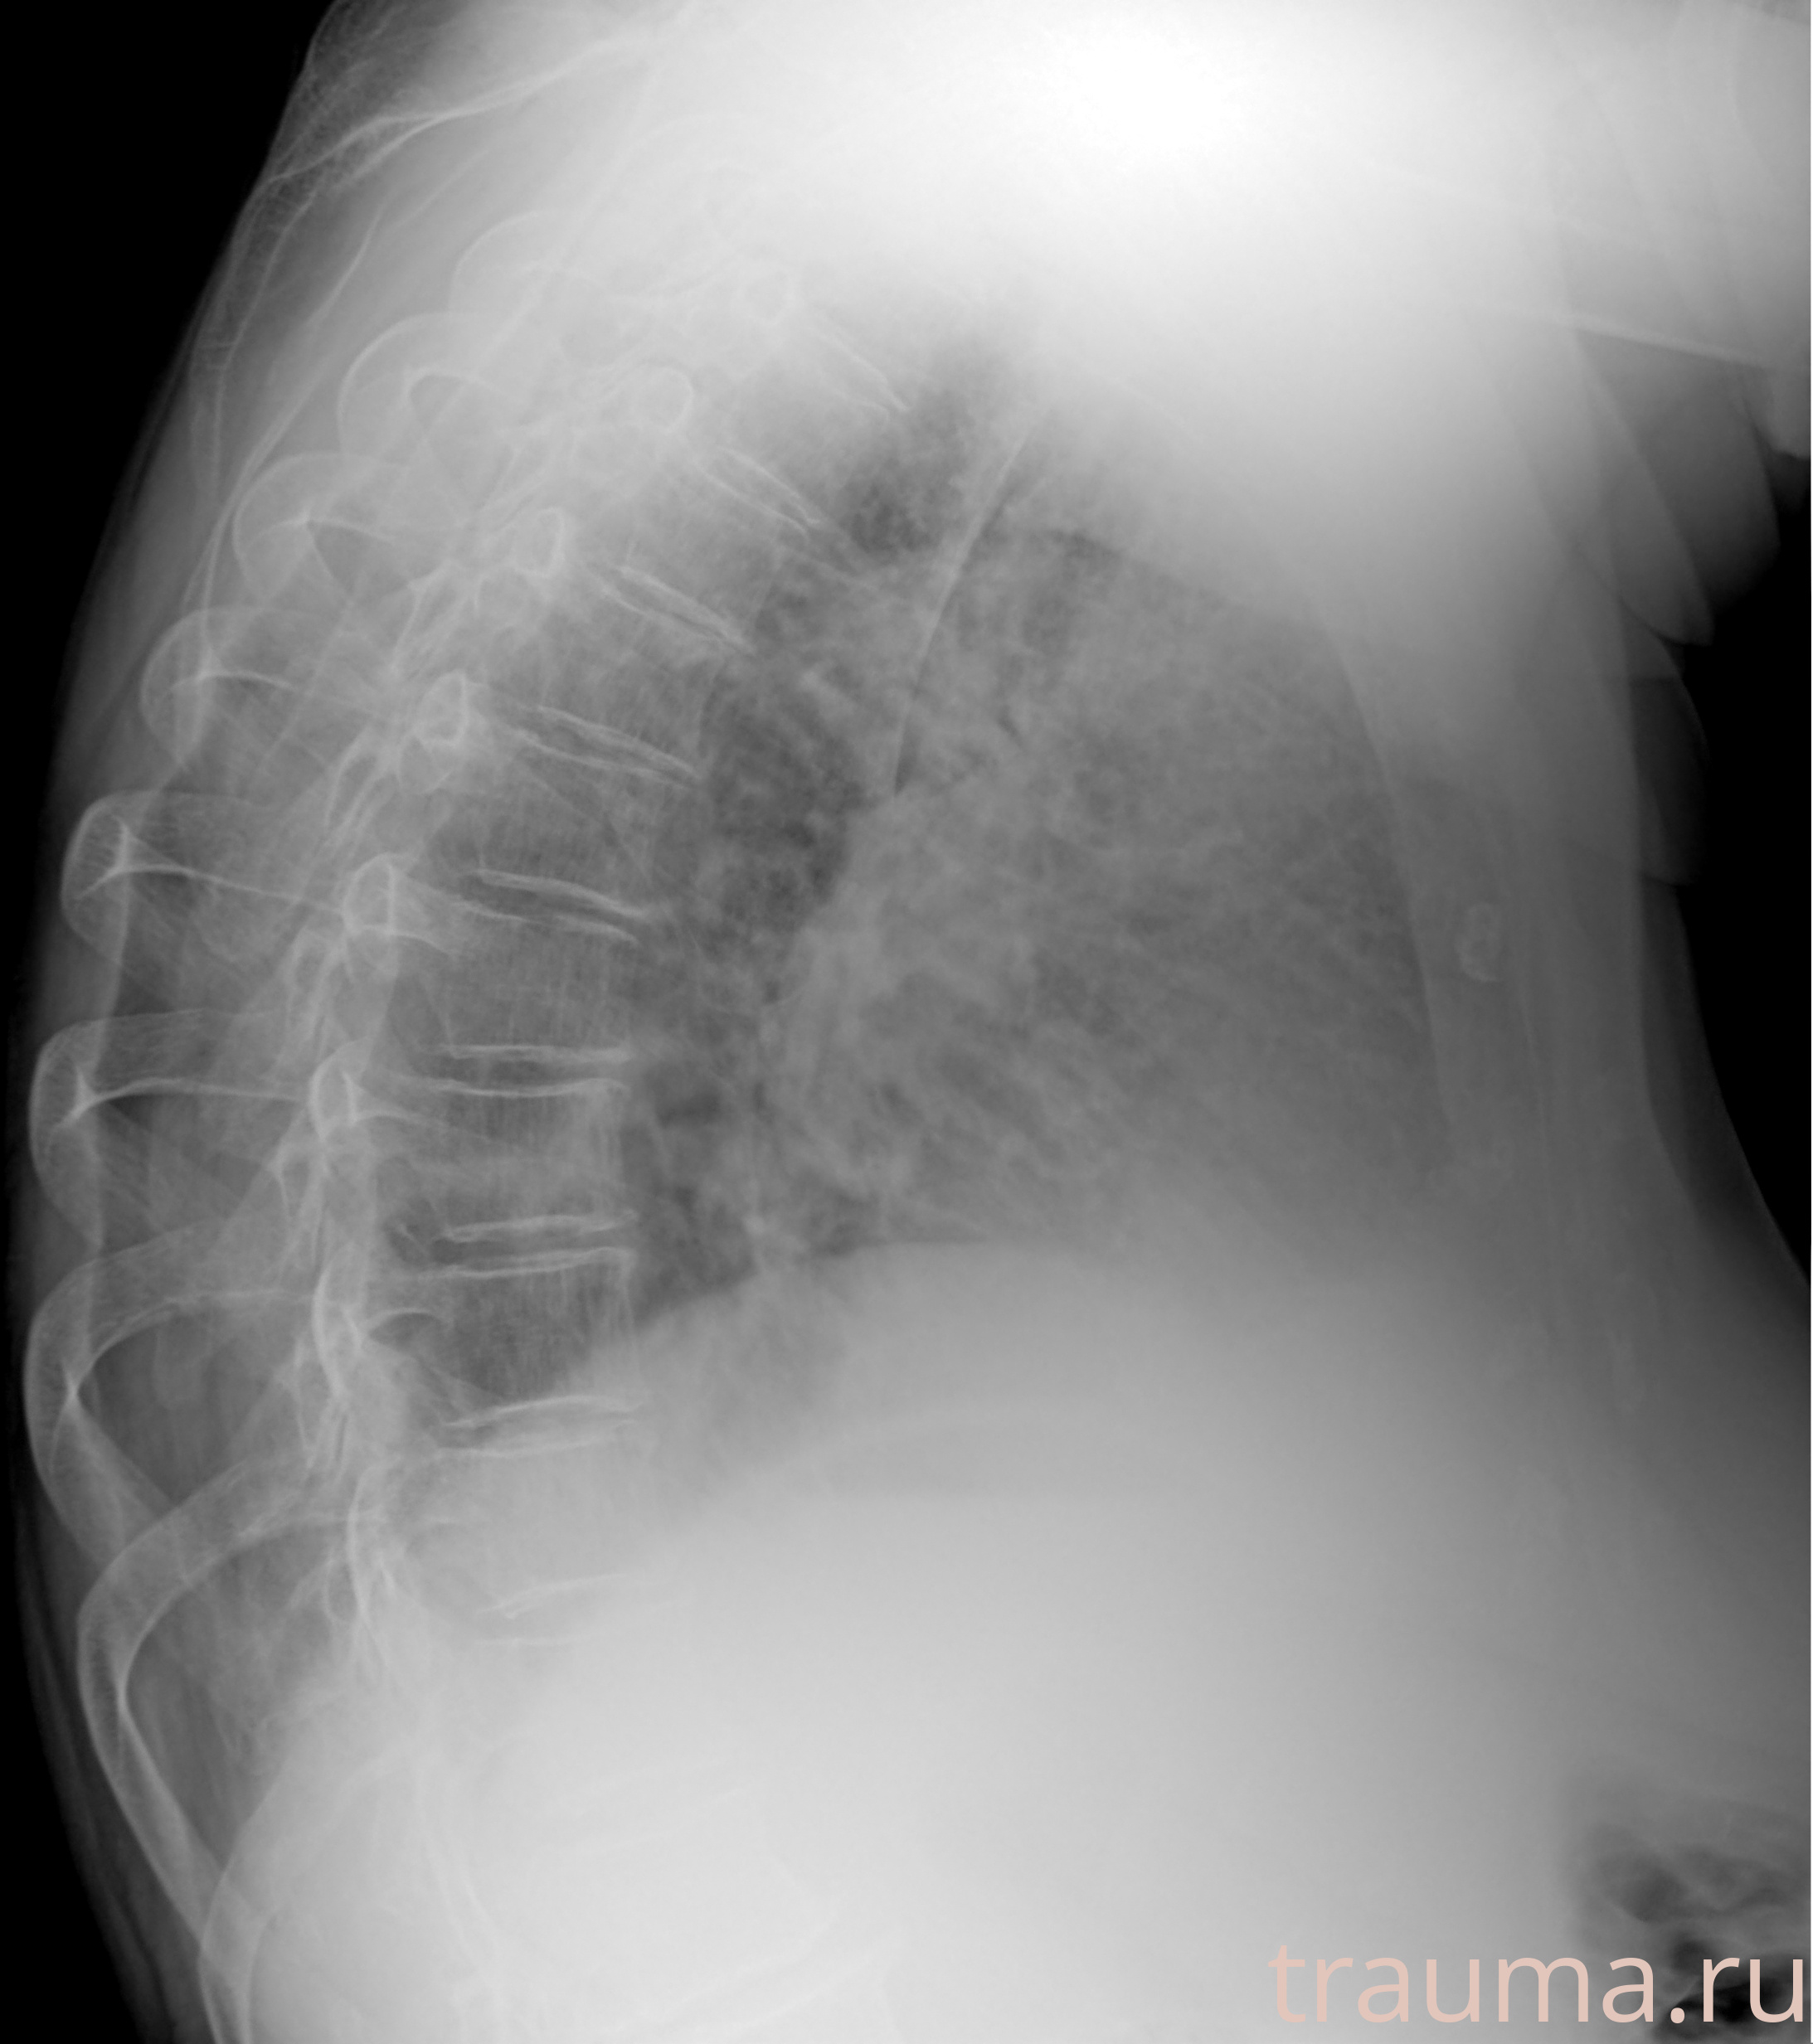

Рентгенограммы

Рентген на дому: по вашему адресу приезжает врач-рентгенолог, травматолог-ортопед с мобильным рентгеновским аппаратом, проводит диагностику травмы или заболевания, делает необходимые рентгенограммы, дает рекомендации по дальнейшему лечению. Получить качественные снимки в домашних условиях возможно благодаря уникальной методике, разработанной МосРентген Центром для института  Склифосовского